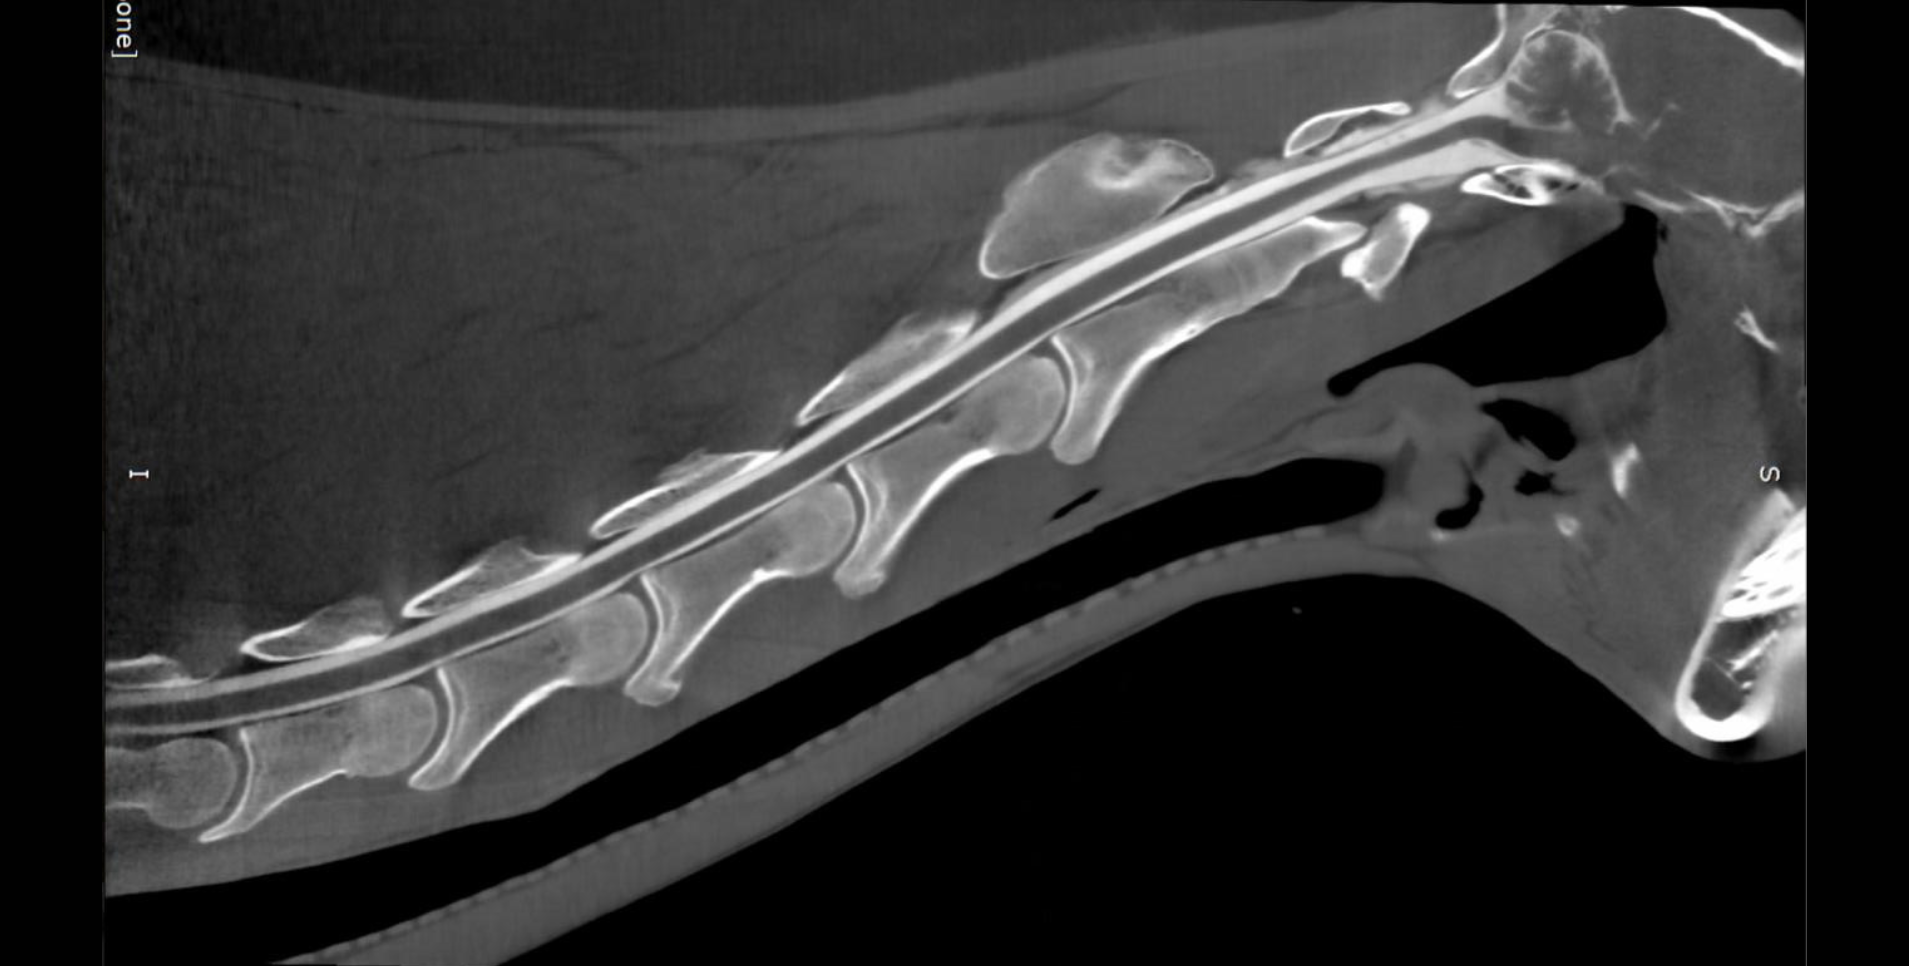

STANDING LIMB IMAGING